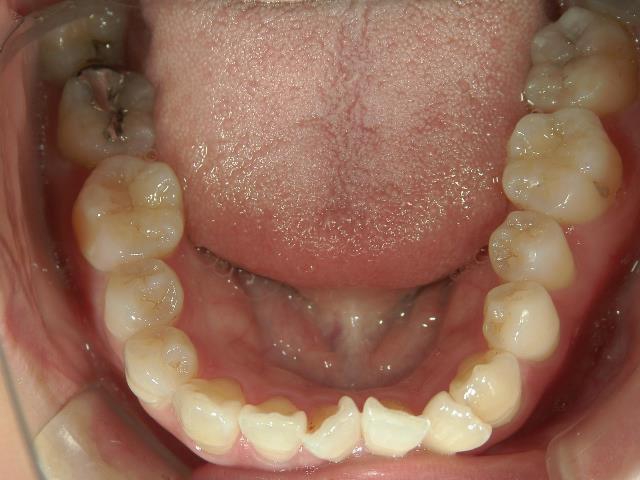

矯正歯科 治療前矯正歯科 治療前

矯正歯科 治療前 アクア/上顎1年4カ月→プチワイヤー矯正/上下顎2年

矯正_灰色.pngno.37_7548_治療前_上.JPG矯正_灰色.png

矯正_灰色.pngno.37_7548_治療前_下.JPG矯正_灰色.png